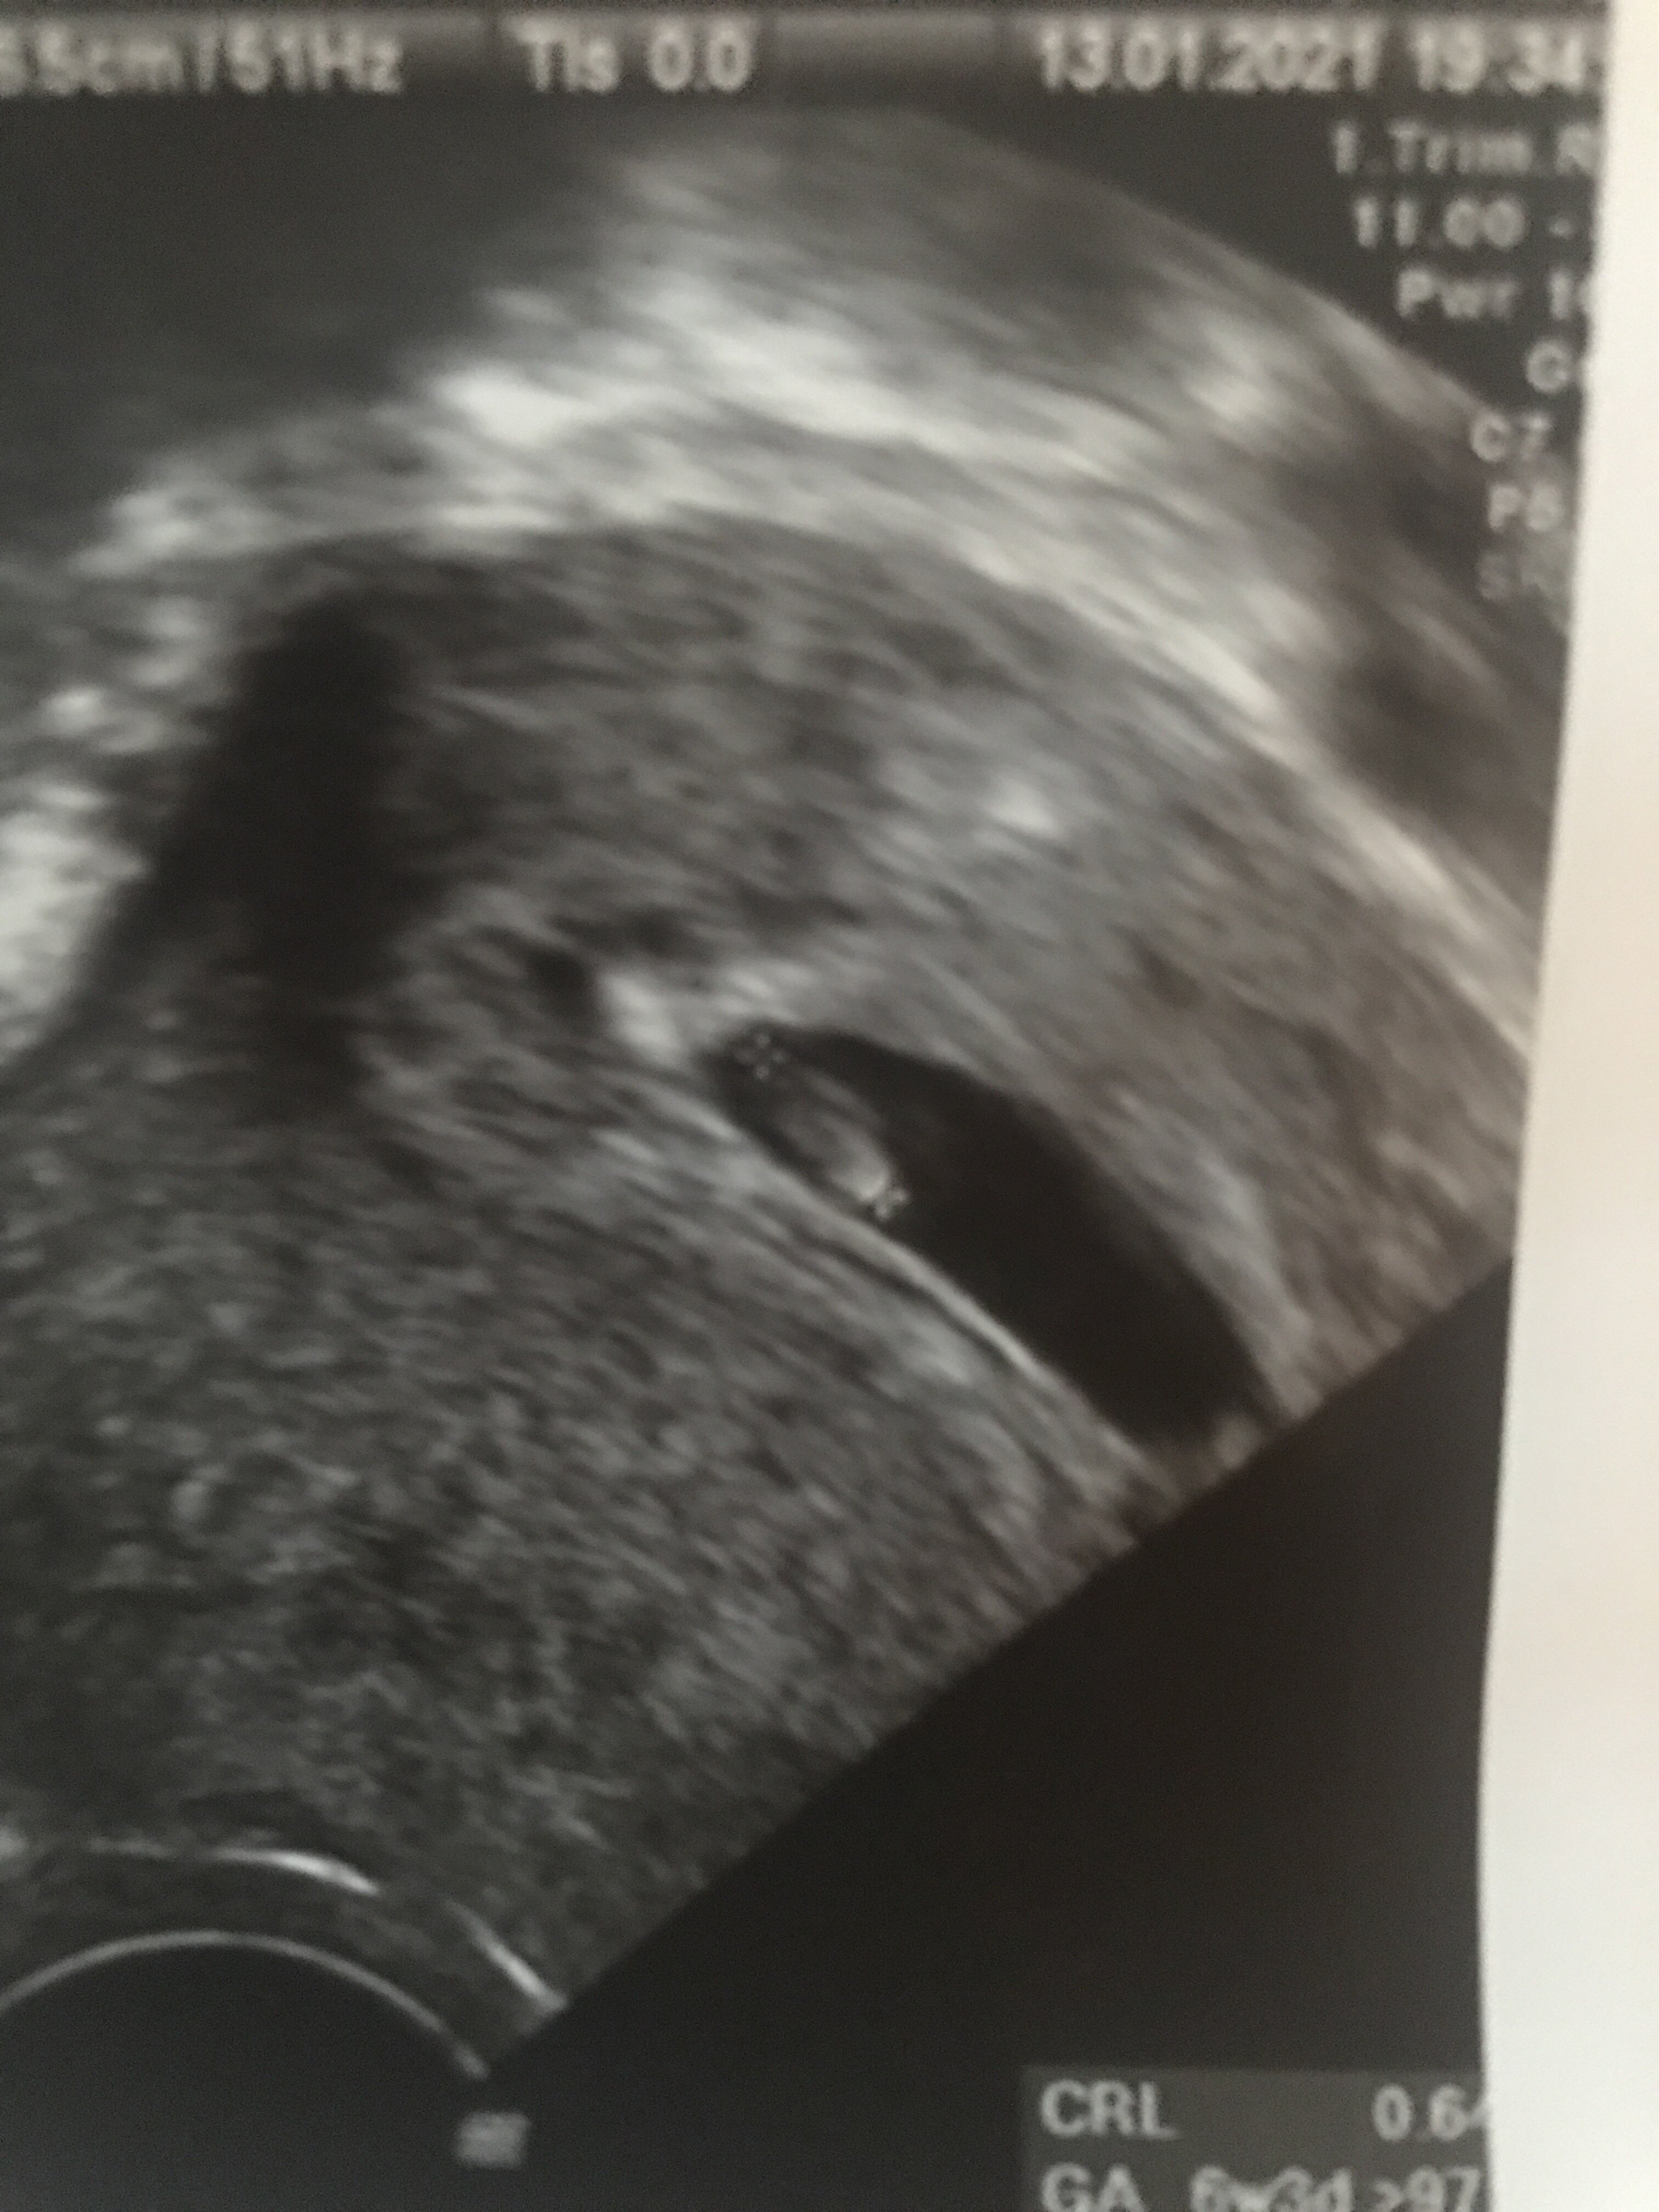

W załączniku mój pęcherzyk 6t6d.

• 05AE86C0-E413-49CC-AD3A-1033E78EEC6F.jpeg

05AE86C0-E413-49CC-AD3A-1033E78EEC6F.jpeg

903,2 KB · Wyświetleń: 2 355